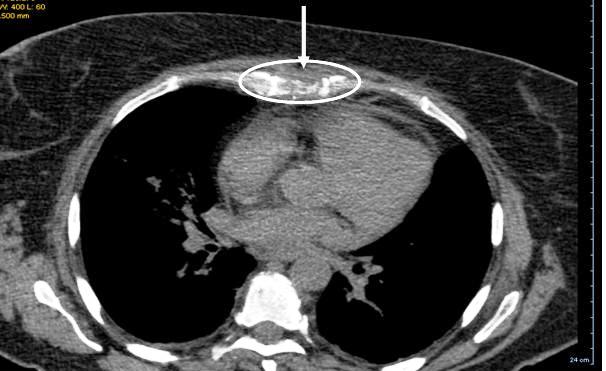

Figure 1

. Scanner view of lytic lesions on the sternum